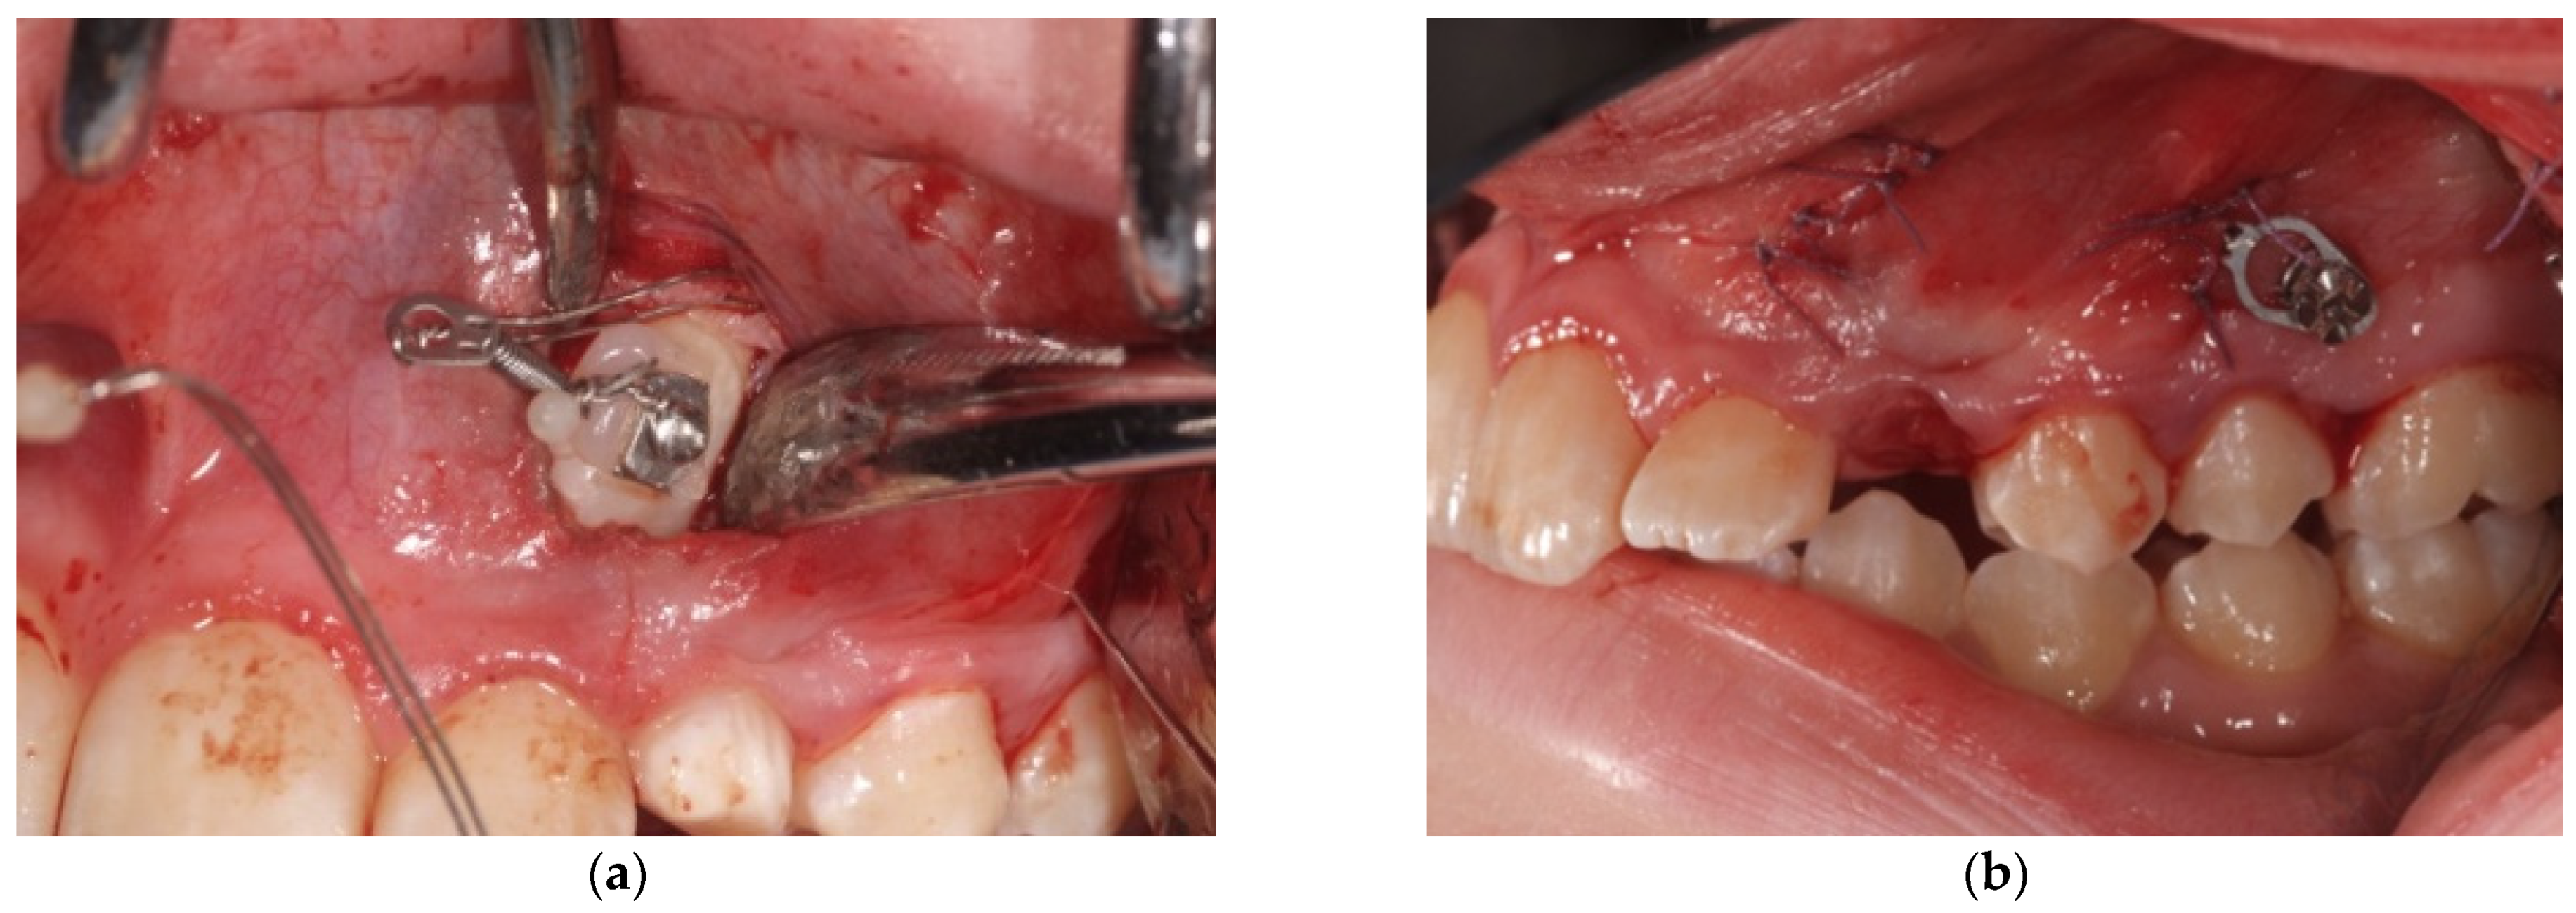

- After a good hemostasis is reached, the button is attached to the buccal canine crown’s surface, following all necessary steps including enamel etching with 37% orthophosphoric acid for 30 s and applying adhesive. Therefore, the button is connected by means of a metal ligature to a 150 gr closed coil spring (NiTi). At the distal end of the NiTi coil, another metal ligature is inserted to facilitate the passage of the traction system under the subperiosteal tunnel (Figure 5);

- Then, the second metallic ligature is inserted in the subperiosteal tunnel to leak out from the posterior vertical incision. Alternatively, the Klemmer forceps can be inserted through the posterior vertical incision and pushed forward inside the tunnel until its end is visible from the anterior incision, to take the spring end and train it posteriorly until it exits from the rear end of the tunnel;

- After checking the primary stability, the miniscrew is connected to the NiTi spring.

- Then, the suture of the surgical wounds is performed with an absorbable Vicryl 4-0 thread;